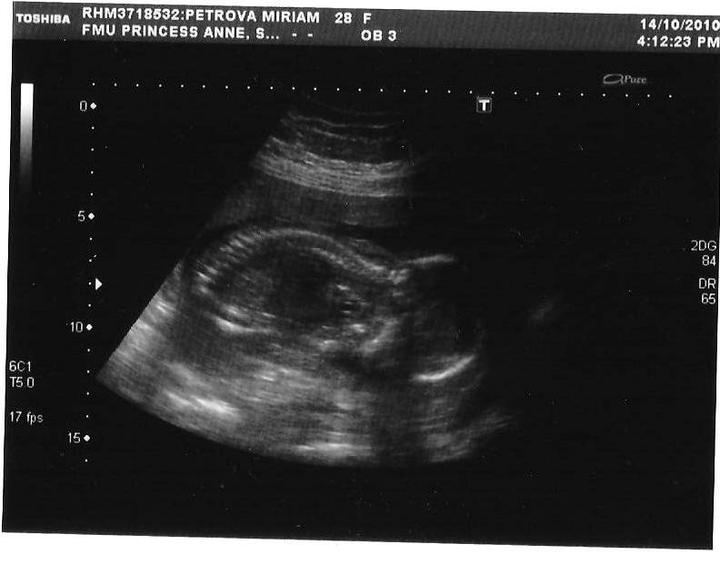

vcera druhy pokusny ultrazvuk, babatko je velmi vtipne, zase ma poslali von sa prejst vypit pol litra koly a aj tak sa nam nechcelo poriadne ukazat. no fotomodelka z neho jednoducho nebude 🙂

babatko tajnostkar, nechcelo nic na ultrazvuku ukazat, ani xichtit sme mu nevideli, lebo lezkalo na brusku (a pre nasu maminu: ani ten svoncek nebolo vidiet). musime sa ist ultrazvukovat este raz 🙂